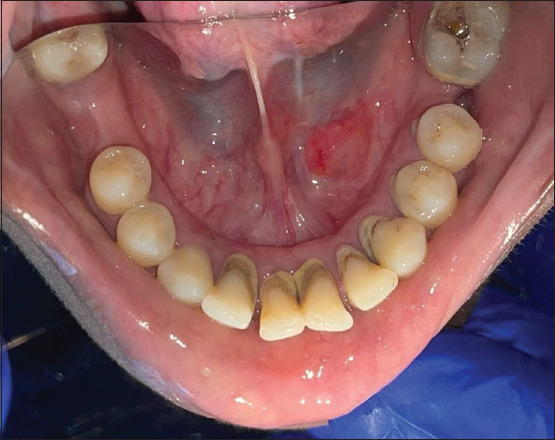

Background: Oral mucoceles are common lesions involving the salivary glands, characterized by mucous extravasation or retention phenomena. Despite their prevalence, they are often underreported, leading to potential diagnostic challenges and oversight of unusual presentations. This retrospective study aimed to analyze the clinical characteristics, demographic trends, and management outcomes of oral mucoceles over a 10-year period.

Materials and methods: A retrospective analysis was conducted on archival data from January 2014 to January 2024. Cases with a confirmed diagnosis of mucoceles based on histopathological examination were included. Data regarding demographic characteristics, anatomical site of mucocele, clinical presentation, biopsy type, and follow-up information were collected and analyzed using descriptive statistics.

Results: Out of 58 clinically diagnosed mucocele cases, 53 were confirmed histopathologically. The mean age of the reviewed cases was 24.3 ± 16.5 years, with a male predominance (60.4%). Mucoceles predominantly affected the lower lip (62.3%), followed by the lip region (13.2%). Excisional biopsy was the preferred treatment modality (88.7%), with the mucous extravasation phenomenon being the predominant histopathological diagnosis (98.1%). Recurrence was observed in one case (1.9%).

Conclusion: This study contributes to understanding the prevalence, clinical characteristics, and management outcomes of oral mucoceles. The findings emphasize the importance of accurate diagnosis and appropriate management strategies to optimize patient care and outcomes.